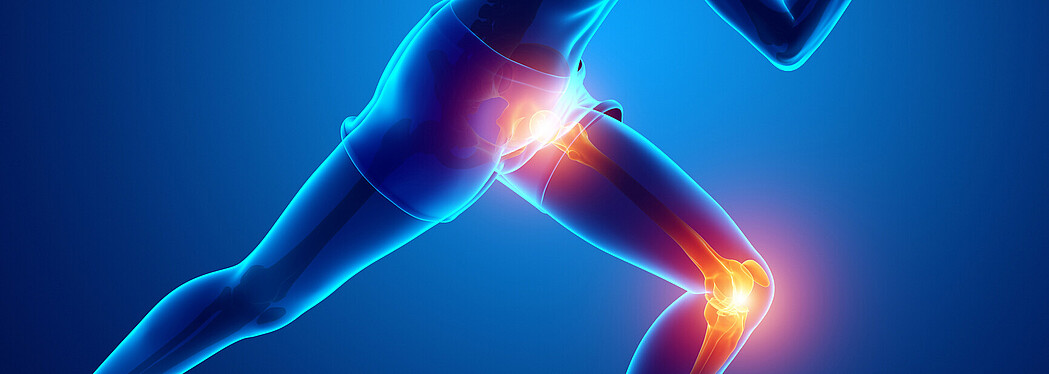

GLAD - Besser leben mit Arthrose

GLA:D® steht für «Good Life with Osteoarthritis in Denmark» und bedeutet «Besser leben mit Arthrose in Dänemark». Seit 2019 wird diese erfolgreiche Behandlungsmethode auch in der Schweiz angeboten. Ziel des Programms ist es, Menschen mit Arthrose eine bessere Lebensqualität zu ermöglichen.